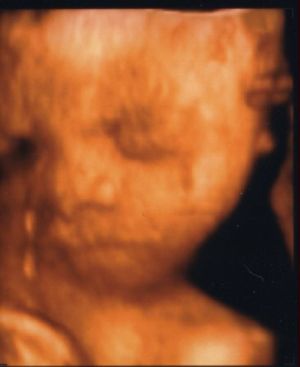

Megy a 3D-s kép! Kép